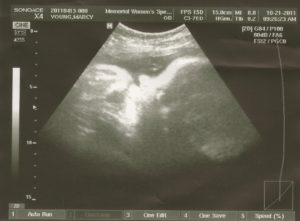

Обычно все плановые ультразвуковые исследования уже сделаны. УЗИ на 39 неделе беременности назначается только в случае уточнения веса и роста плода, развития его органов и систем, а также для определения тактики ведения родов. Внимание уделяется состоянию шейки матки, степени зрелости плаценты, а также тому, есть ли обвитие пуповиной или нет.

Врач проводит полный осмотр беременной: определяет предлежание плода, подвижна или нет головка плода над входом в таз, определяет массу плода и оценивает состояние шейки матка.

Шейка матки на 39 неделе уже начинает укорачиваться и размягчаться, кроме того после отхода слизистой пробки она потихоньку раскрывается. В норме раскрытие шейки до начала родов на 1 см.

На 39 неделе женщине нужно быть очень внимательной к своим выделениям. На этом сроке возможно преждевременное излитие околоплодных вод. Если выделения стали обильнее, обратите внимание на их консистенцию.

В случае появления водянистых выделений нужно срочно обращаться к доктору. Подтекание вод может быть малым, что совершенно не страшно, а может быть обильным.

В таком случае может быть принято решение об экстренном родоразрешении.